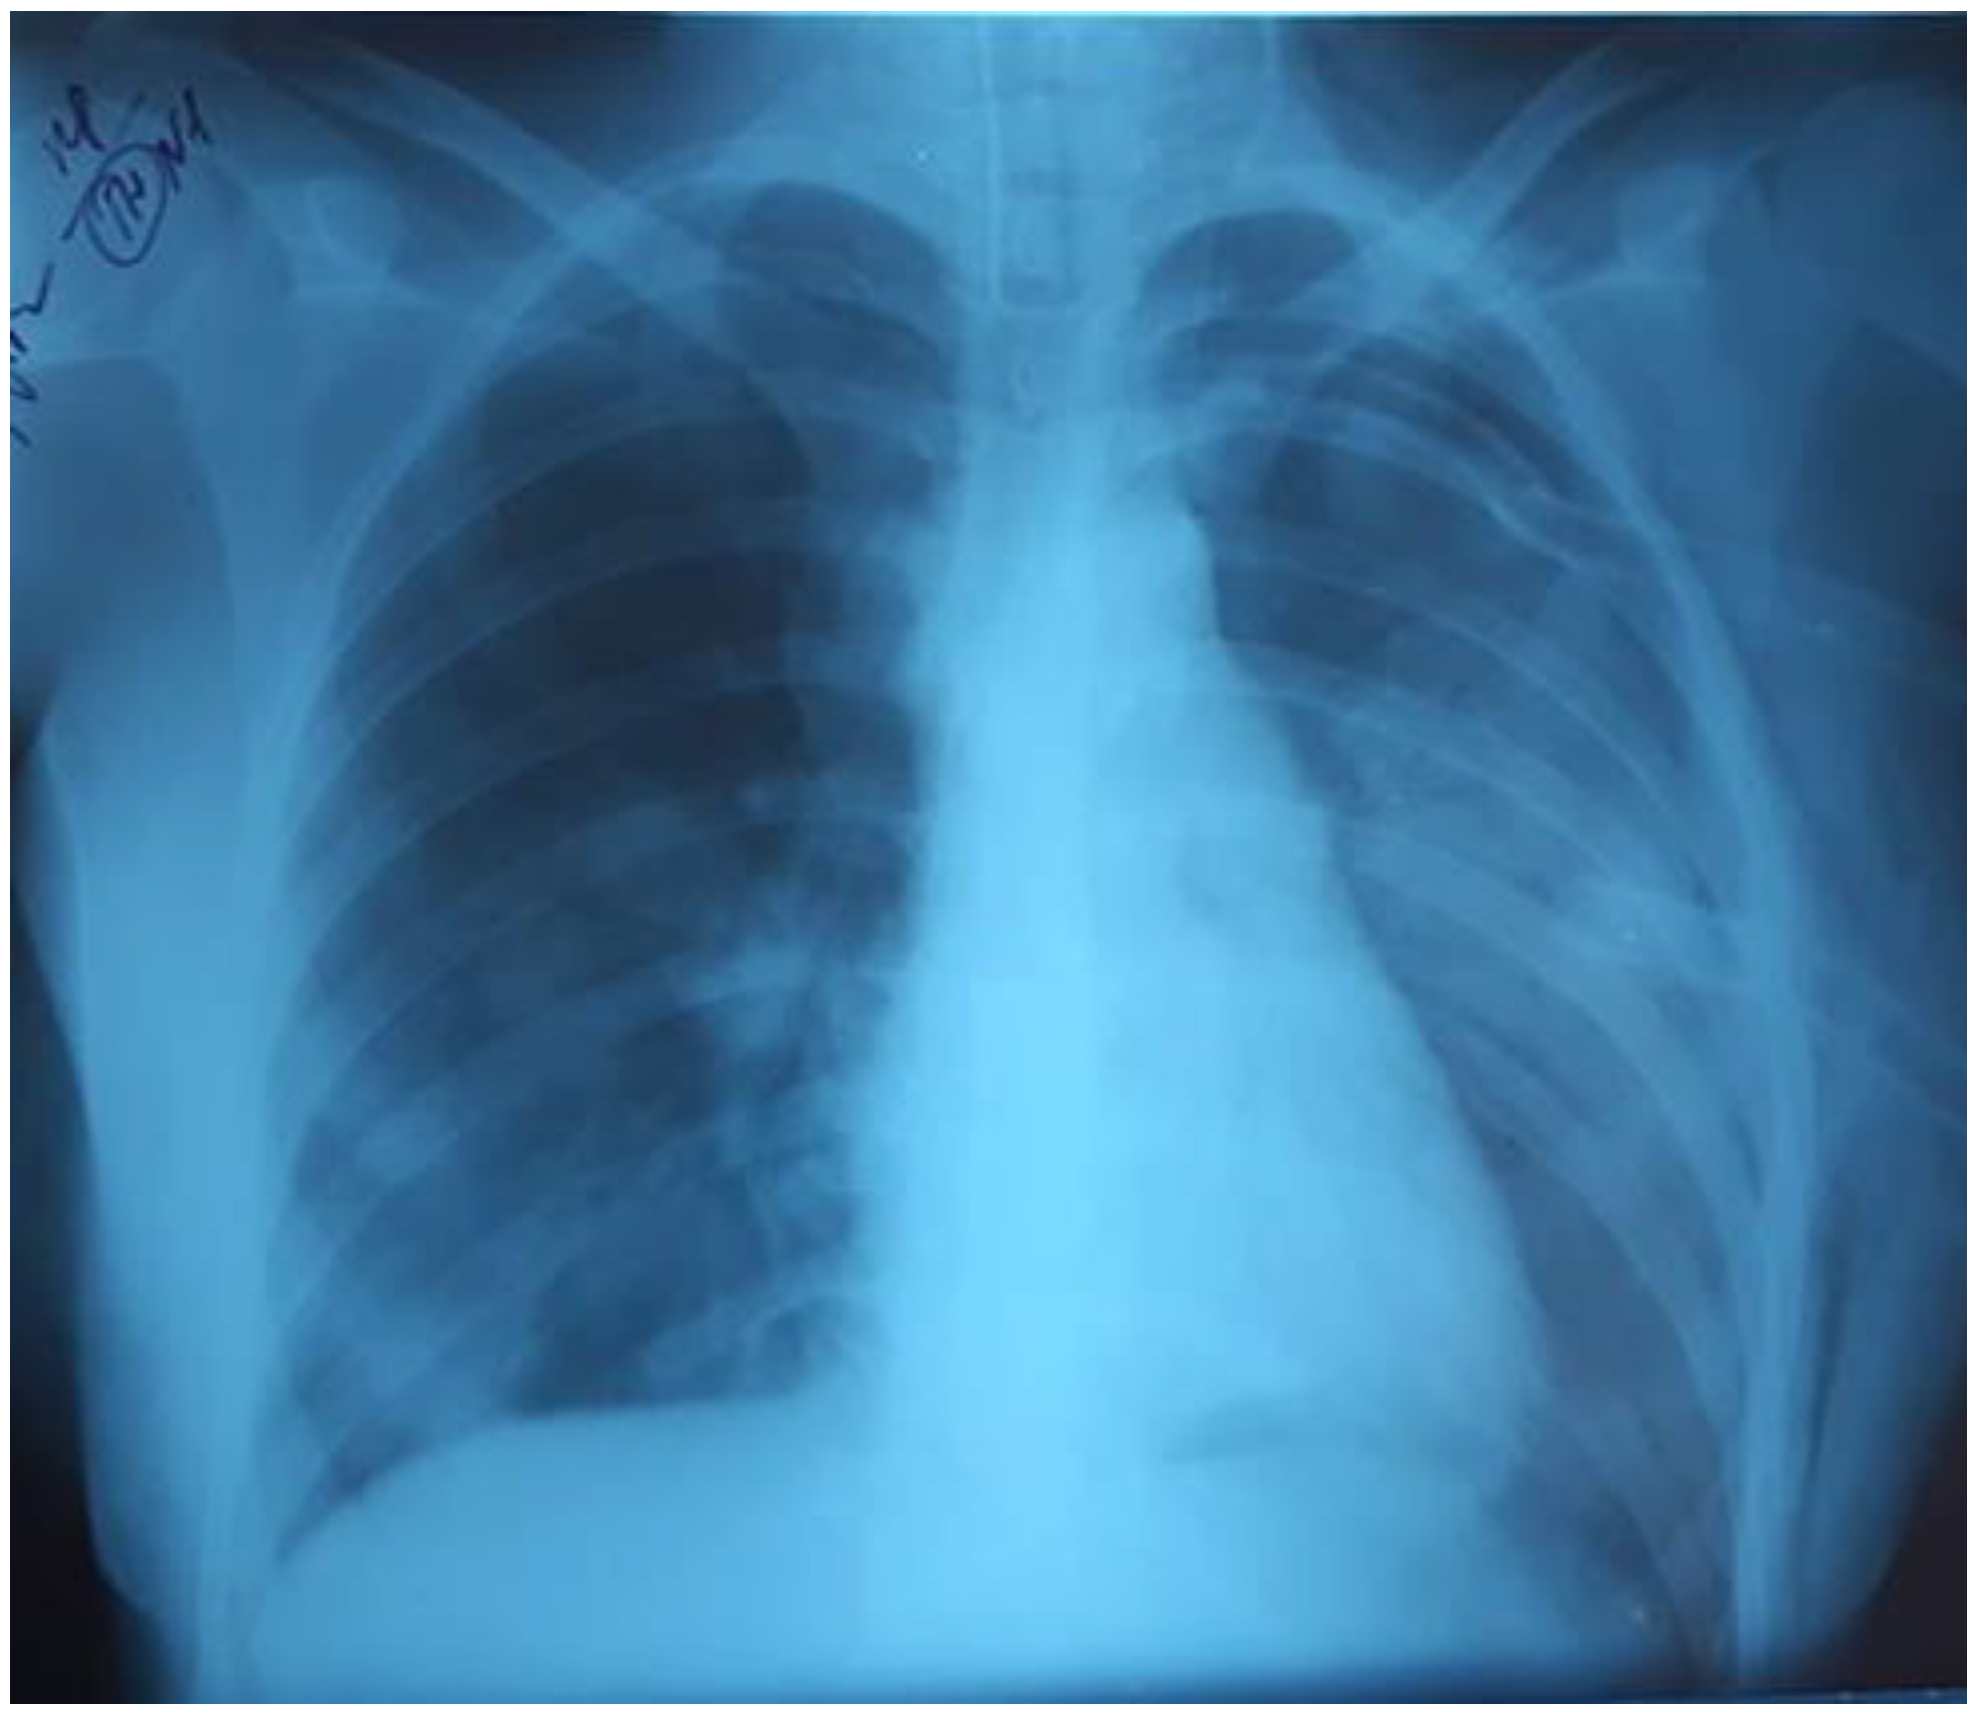

A three-year-old girl (body weight 15 kg) was admitted to the ICU with severe signs of RF. Physical examination revealed shortness of breath, respiratory rate (RR) 72 /min, retraction of intercostal spaces, heart rate (HR) 170/min, sinus tachycardia, SpO2 87%, and body temperature 36.8 °C. Crackles on both sides of the lungs were detected during the auscultation. The chest radiography revealed right-sided focal pneumonia (Figure 1).

Figure 1.

Right-sided focal pneumonia.